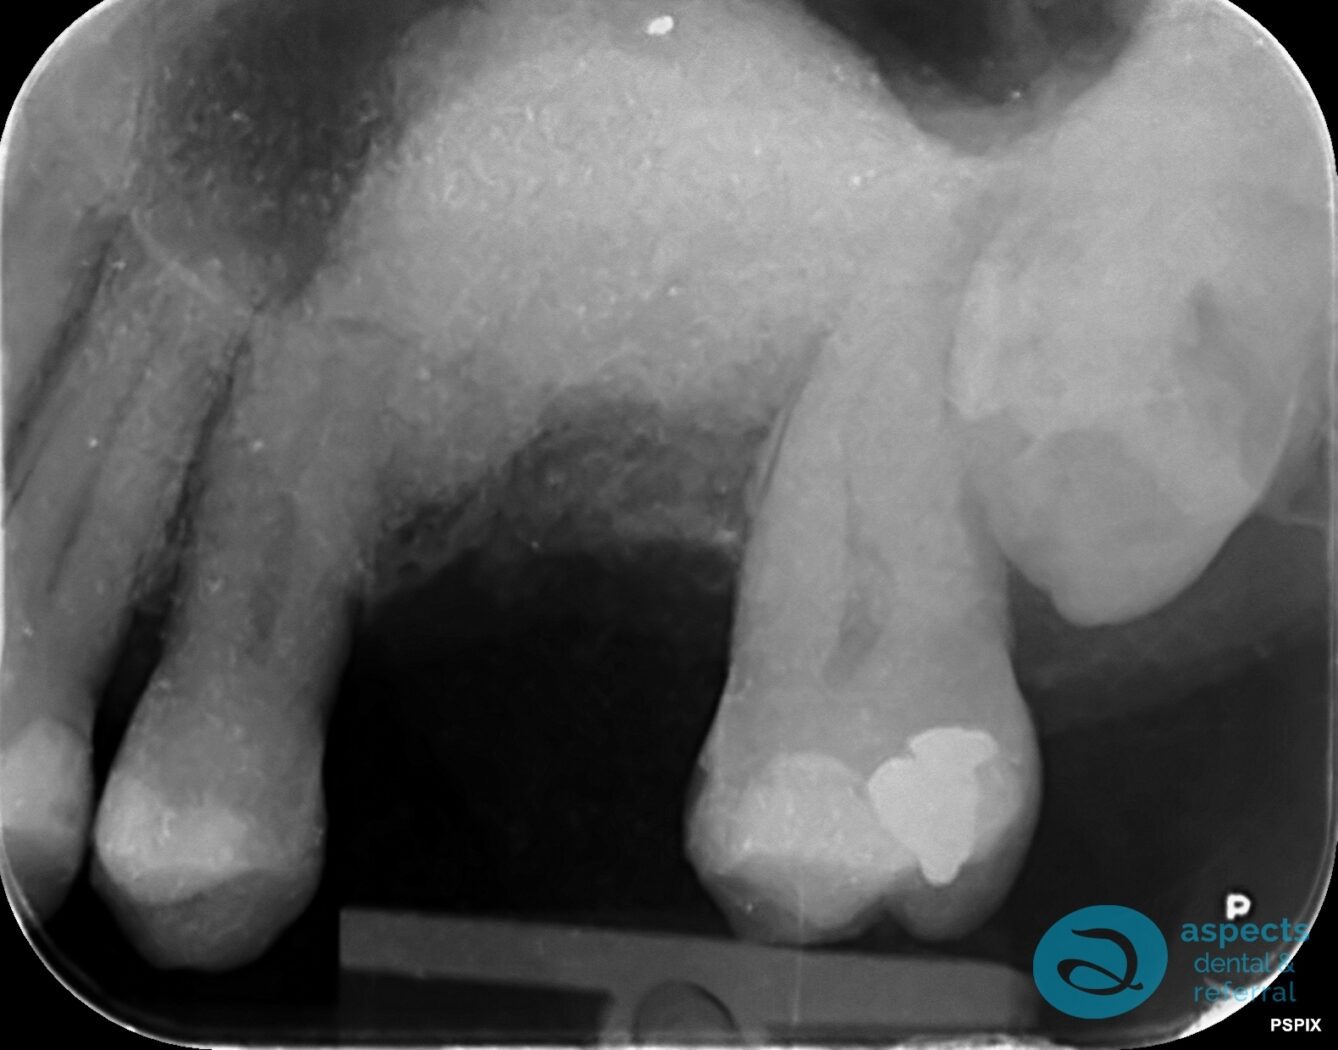

Before Tooth Extraction & Sinus Lift Xray

Our Dental Patient was referred for the extraction of a severely compromised maxillary left molar, with the treatment plan including subsequent Dental Implant placement. Following the extraction, a sinus lift procedure was performed to augment the bone and achieve sufficient vertical height for future implant placement.